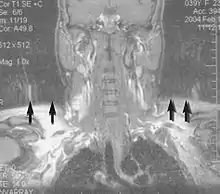

Magnetic resonance angiography (MRA) generates pictures of the arteries to evaluate them for stenosis (abnormal narrowing) or aneurysms (vessel wall dilatations, at risk of rupture). MRA is often used to evaluate the arteries of the neck and brain, the thoracic and abdominal aorta, the renal arteries, and the legs (called a "run-off"). A variety of techniques can be used to generate the pictures, such as administration of a paramagnetic contrast agent (gadolinium) or using a technique known as "flow-related enhancement" (e.g., 2D and 3D time-of-flight sequences), where most of the signal on an image is due to blood that recently moved into that plane (see also FLASH MRI).[39]

Techniques involving phase accumulation (known as phase contrast angiography) can also be used to generate flow velocity maps easily and accurately. Magnetic resonance venography (MRV) is a similar procedure that is used to image veins. In this method, the tissue is now excited inferiorly, while the signal is gathered in the plane immediately superior to the excitation plane—thus imaging the venous blood that recently moved from the excited plane.[40]